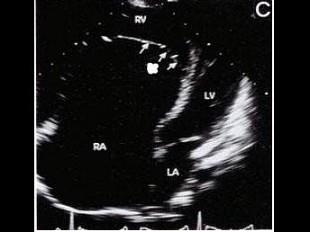

该病例最可能的诊断?(?)A.右室双腔B.三尖瓣缺如C.异位腱索D.三尖瓣下移E.室间隔缺损

问题 该病例最可能的诊断?(?)

选项 A.右室双腔 B.三尖瓣缺如 C.异位腱索 D.三尖瓣下移 E.室间隔缺损

答案 D